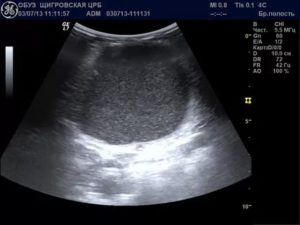

Этот показатель определяется на УЗИ. В полость вводится специальный датчик, благодаря которому на экране отображаются все внутренние органы. Врач может оценить строение матки, посмотреть размеры яичников. Если вещество отсутствует, то оно не визуализируется.

Достаточно часто свободная жидкость за маткой является признаком патологии внутренних органов женщины. Определить на УЗИ точный объем такого образования крайне сложно, потому что она растекается между репродуктивными органами. Медики разработали определенные критерии, позволяющие оценить состояние жидкости в позадиматочном пространстве (измеряется длина вертикального уровня образования):

На УЗИ врач увидит небольшое ее количество, что является нормой. Жидкость через несколько дней рассасывается и не доставляет женщине неудобств.